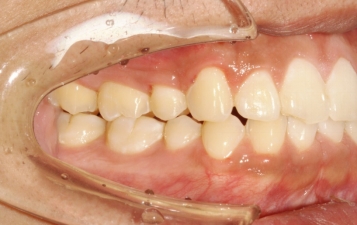

口内检查 :上下牙弓均为卵圆形 左右基本对称 上颌牙弓轻度拥挤 下颌缺失一颗下切牙

左右侧磨牙均为一类咬合关系,前牙深覆合、深覆盖。

临床 前牙深覆合,深覆盖,后牙中性关系

上下前牙唇倾

双唇前突

治疗预计效果和实际效果

治疗前后对比